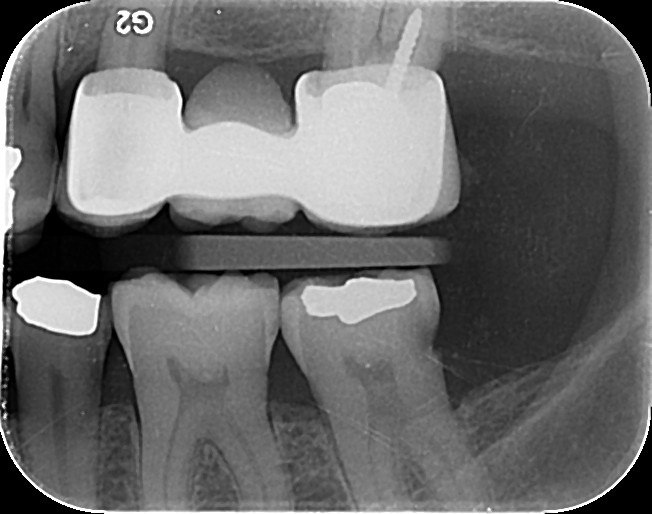

4. Which surface needs restoration?